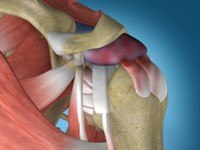

Shoulder Stabilization

Shoulder instability is a chronic condition that causes frequent dislocations of the shoulder joint. A dislocation occurs when the end of the humerus (the ball portion) partially or completely dislocates from the glenoid (the socket portion) of the shoulder. A partial dislocation is referred to as a subluxation whereas a complete separation is referred to as a dislocation.

Latarjet

The shoulder joint provides a wide range of movement to the upper extremity but overuse or trauma can cause instability to the joint. The Latarjet procedure is a surgical procedure performed to treat shoulder instability by relocating a piece of bone with an attached tendon to the shoulder joint.